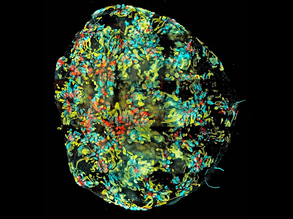

Killing to Cure